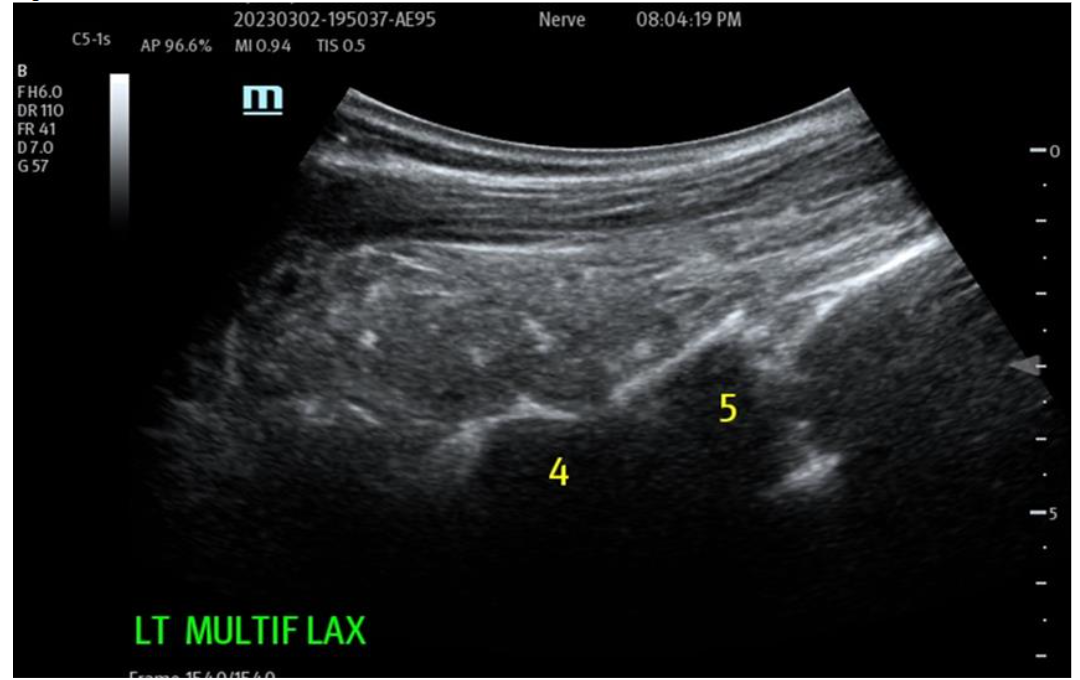

Figure 3: Pre-operative treatment site Multifidus (loss of function dynamically) at L4-5 and above. Multiple targets IM for return of function and architecture. NOTE: Likely most common site that accompanies Lumbar facets pain seen together and is treated.

Muscular/Scar Repair: The ability of the biocellular mixture in the repair of torn, damaged or failed muscular structures is quite remarkable. This is accentuated in light of the difficulties relative to internal muscle repair of damage as seen in trauma or invasive surgery. Often rapid responses are realized, with both avoidance of scarring OR the reduction of scarring present has been well shown in many clinical cases. With enhanced vascularity and perfusion within the damaged muscular tissues, limited or less scar formations are important advantages. Some Providers define a ”toxic” inflammatory reactions as those that lead to tissue scarring. This is seen in unstable or excessive inflammatory scar reactions which are not desirable. Avoidance of excesses or hypertrophic scarring is a clear advantage to wound healing and long-term outcomes for patients. Nanofat stem/stromal elements are capable of forming smooth, skeletal and cardiac muscle. Biocellular therapy helps a more stable and less inflammatory environment. This coupled with the existing damaged muscle can lead to excellent reformation and return to function. This modality is becoming very common to include direct intramuscular guided placements to improve the internal architecture (sonographic echotexture restoration), and confirmed with dynamic testing of the musculature during the ultrasound from diagnostic and treatment when tracked in follow up examinations.